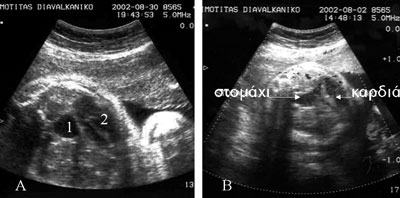

Εικόνα 2. Διαφραγματοκήλη εμβρύου. Τα δύο όργανα, καρδιά και στόμαχος του εμβρύου, σε εγκάρσια τομή του θώρακα, προβάλλονται στο ίδιο επίπεδο. Η απώθηση της καρδιάς στο θωρακικό τοίχωμα σε συνδυασμό με την σαφώς περιορισμένη έκταση του πνευμονικού παρεγχύματος αποτέλεσαν, προγεννητικά, δυσμενή προγνωστικό δείκτη. Το νεογνό, παρά την εντατική προσπάθεια ανάνηψης κατέληξε εντός του πρώτου 24ώρου. Διαπιστώθηκε παντελής έλλειψη έκπτυξης των πνευμόνων.

Εικόνα 3. Καλόηθες πολύχωρο τεράτωμα κόκκυγος σε έμβρυο ηλικίας 20 εβδομάδων με χαρακτηριστική εικόνα ωοθήκης ύστερα από διέγερση (σε επιμήκη και εγκάρσια τομή).